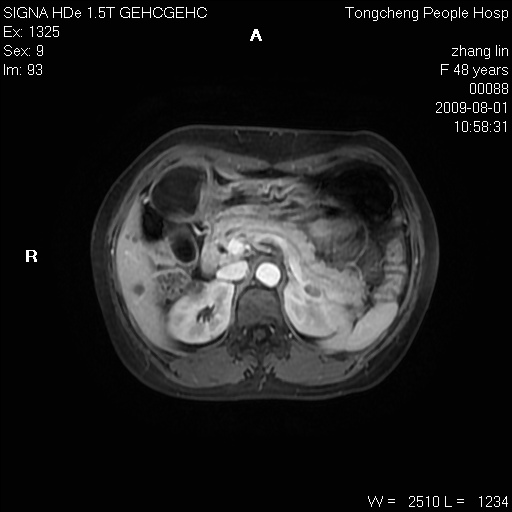

女,48岁。健康体检,彩超发现右肾占位性病变。平素健康。

临床诊断:右肾占位性病变,性质待定(囊肿?肿瘤?)。

上中腹部mr平扫+增强扫描,图像如下:

右肾上极见一类圆形病灶,t1wi呈等信号t2wi呈等高混杂信号,三期增强无强化,边界清---考虑囊肿出血。

同反相位均表现为等信号,病变无强化,考虑含蛋白的囊肿可能,弥散加权相或许有些帮助,

慢性胆囊炎